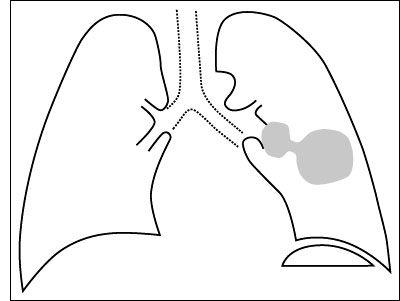

Esquema 25 Comentario placa 25 La sombra irregularmente redondeada del 1/3medio izquierdo tiene un diámetro mayor de 5 - 6 cm, constituyendo una masa. Sus bordes son irregulares y probablemente existe en el hilio izquierdo una imagen nodular de unos 2 cm que podría ser una adenopatía. El conjunto es sugerente de neoplasia y obliga a completar el estudio con los exámenes que permitan comprobar o descartar esta hipótesis. Examine y describa la placa 26 |